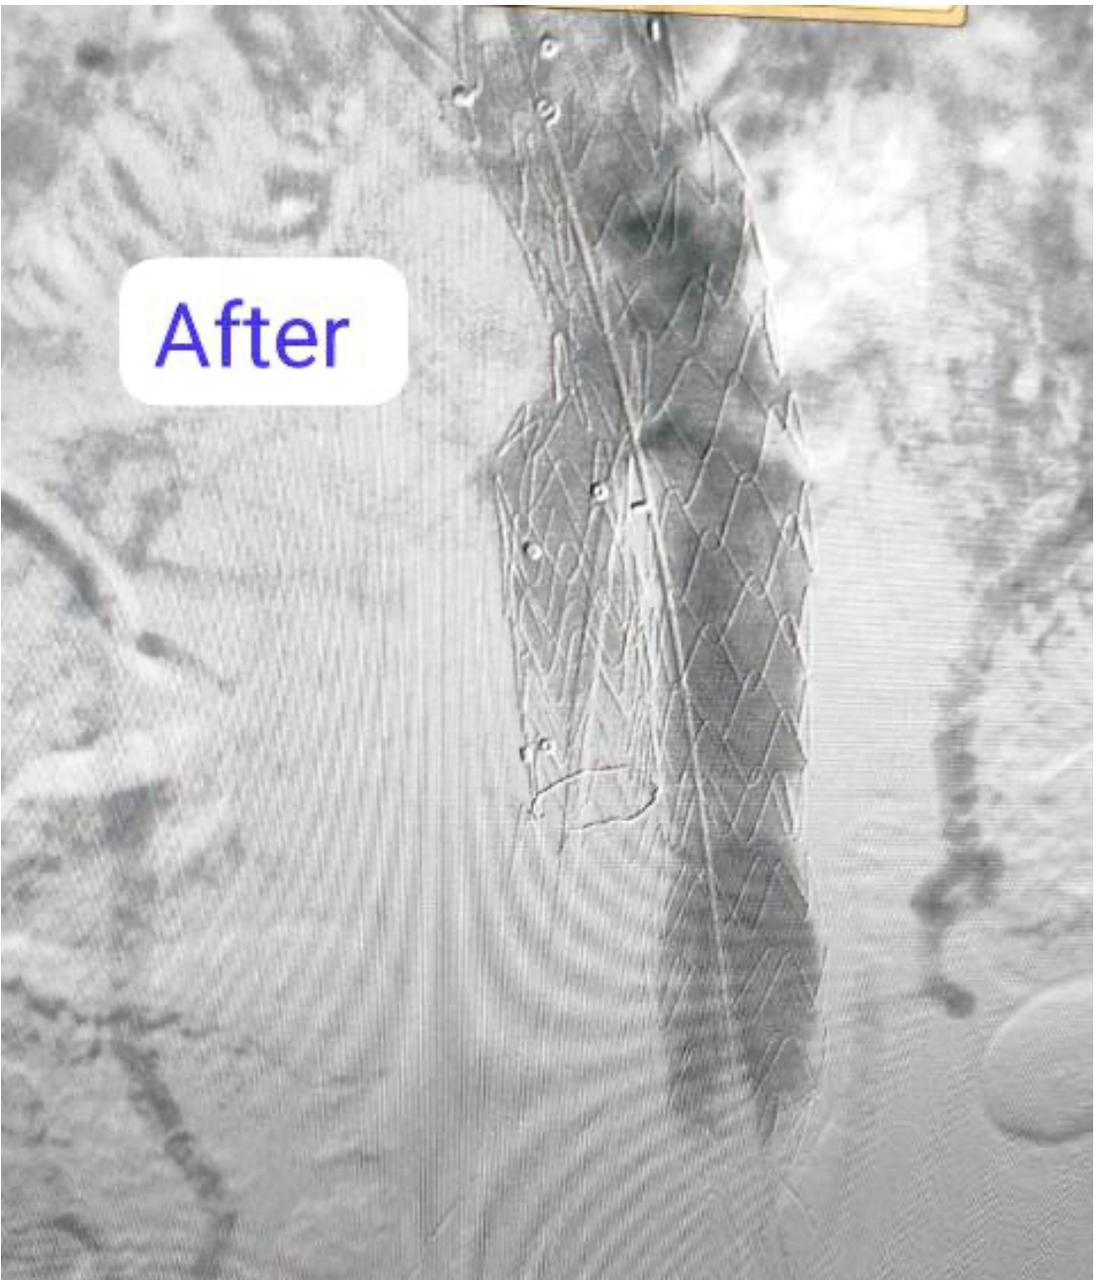

نجح فريق بقسم جراحة الأوعية الدموية بـ مستشفى بدر التابعة لكلية الطب جامعة حلوان، في إجراء تركيب قسطرة دقيقة جدًا لمريض يعاني من تمدد كبير في الشريان الأورطي والشريان الحرقفي الأيمن، حيث تم تثبيت دعامات مغطاة على هذين الشريانين لمنع انفجارهما، مما ساهم في إنقاذ حياته.